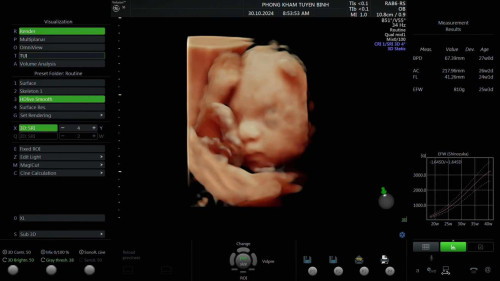

E bầu 25tuần 1ngày con 800g bé quá không các mon